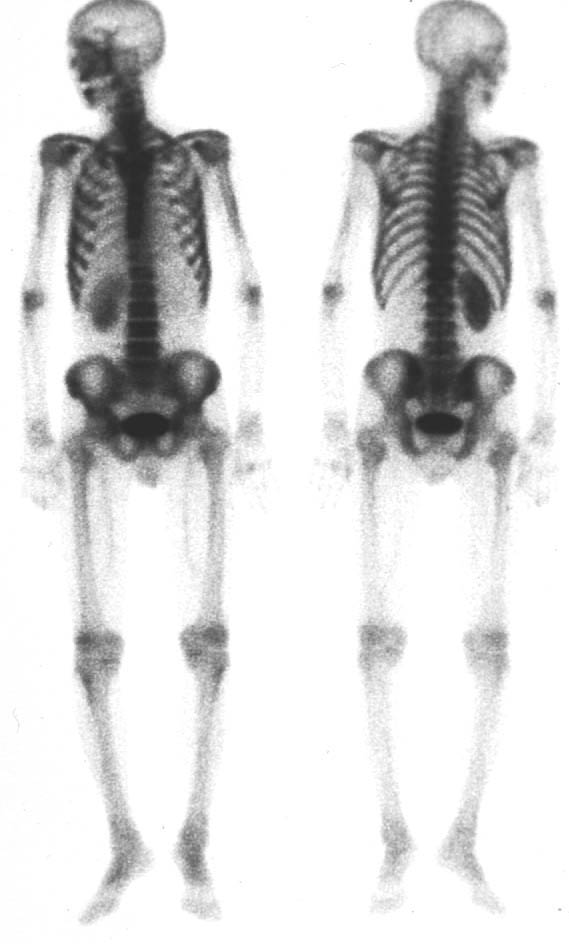

| 第196回定例研究会(1997.6) 骨シンチ『異常集積の少ない骨転移』 | 神奈川県立がんセンター | 小野 慈 |

| 第196回定例研究会(1997.6) 骨シンチ検査の基礎講座 | 神奈川県立循環器呼吸器病センター | 大島 正行 |

(2)compartment解析に関しては代表的なものは、1-compartment model(秀毛らの非線形model(Fig.3)に始まるが、篠原が報告した如く線形modelでの短時間に演算可能な方法でも実用的であった。Veraらが唱えた3-compartment modelは採血を伴うmodel式を利用しており、やや煩雑さを伴っている。河らが提唱した5-compartment modelは複雑な計算式を必要としているが、肝最大除去率(Rmax)を算出可能である。(Fig.4)病的 hotなし。 | 第12胸椎に骨溶解像。 | 第12胸椎に 低信号域。 |

![]() | ![]() | ![]() |

| ・全身シンチ | ||||

| コリメータ | 収集マトリックス | ピクセルサイズ | 収集条件 | 撮像方向 |

| mm/Pixel | (スキャンスピード) | |||

| LEHR | 256×1024 | 2.0 | 10〜15cm/min | ANT,POST |

| 512×2048 | 1.0 | |||

| ・部分シンチ | ||||

| mm/Pixel | (カウントorタイム) | |||

| LEHR | 512×512 | 0.6〜1.0 | 1000K(8分) | 異常部位多方向 |